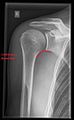

Shoulder imaging

Imaging of the shoulder includes ultrasound, X-ray and MRI, and is guided by the suspected diagnosis and presenting symptoms.

Conventional x-rays and ultrasonography are the primary tools used to confirm a diagnosis of injuries sustained to the rotator cuff. For extended clinical questions, imaging through Magnetic Resonance with or without intraarticular contrast agent is indicated.

Hodler et al. recommend starting scanning with conventional x-rays taken from at least two planes, since this method gives a wide first impression and even has the chance of exposing any frequent shoulder pathologies, i.e., decompensated rotator cuff tears, tendinitis calcarea, dislocations, fractures, usures, and/or osteophytes. Furthermore, x-rays are required for the planning of an optimal CT or MR image.[22]

X-ray

Projectional radiography views of the shoulder include:

AP-projection 40° posterior oblique after Grashey

The body has to be rotated about 30 to 45 degrees towards the shoulder to be imaged, and the standing or sitting patient lets the arm hang. This method reveals the joint gap and the vertical alignment towards the socket.[23]

Transaxillary projection

The arm should be abducted 80 to 100 degrees. This method reveals:[23]

• The horizontal alignment of the humerus head in respect to the socket and the lateral clavicle in respect to the acromion

• Lesions of the anterior and posterior socket border, or of the tuberculum minus

• The eventual non-closure of the acromial apophysis

• The coraco-humeral interval

Y-projection

The lateral contour of the shoulder should be positioned in front of the film in a way that the longitudinal axis of the scapula continues parallel to the path of the rays. This method reveals:[23]

• The horizontal centralization of the humerus head and socket

• The osseous margins of the coraco-acromial arch and hence the supraspinatus outlet canal

• The shape of the acromion

This projection has a low tolerance for errors and, accordingly, needs proper execution.[23] The Y-projection can be traced back to Wijnblath’s 1933 published cavitas-en-face projection.[24]